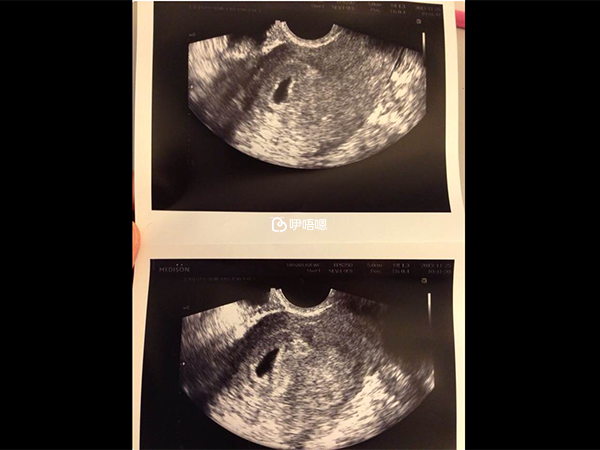

血值非常好,看上去還有雙胞胎的可能,接下來讓一週後驗血,心情又開始忐忑了,擔心血值翻倍,我就每天驗尿,看到了兩道槓心裡踏實。11月25日移植第21天又去了醫院,HCG〉10000,還給了一張胎囊的小照片。

此後我開始有強烈的孕反應了,一連3天吃不下東西,度日如年,熬到12月3日到醫院看到了胎心的B超圖,一顆心終於落了地,我向鹽谷院長要了一個擁抱,幸福的眼淚在那一刻終於止不住了。。。